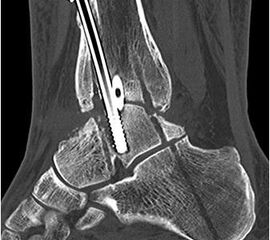

• Primäre oder posttraumatische Arthrose des OSG und USG (Abbildung 1, Abbildung 2).

• Revision einer gescheiterten Fusion des OSG/ USG (Abbildung 3, Abbildung 4).